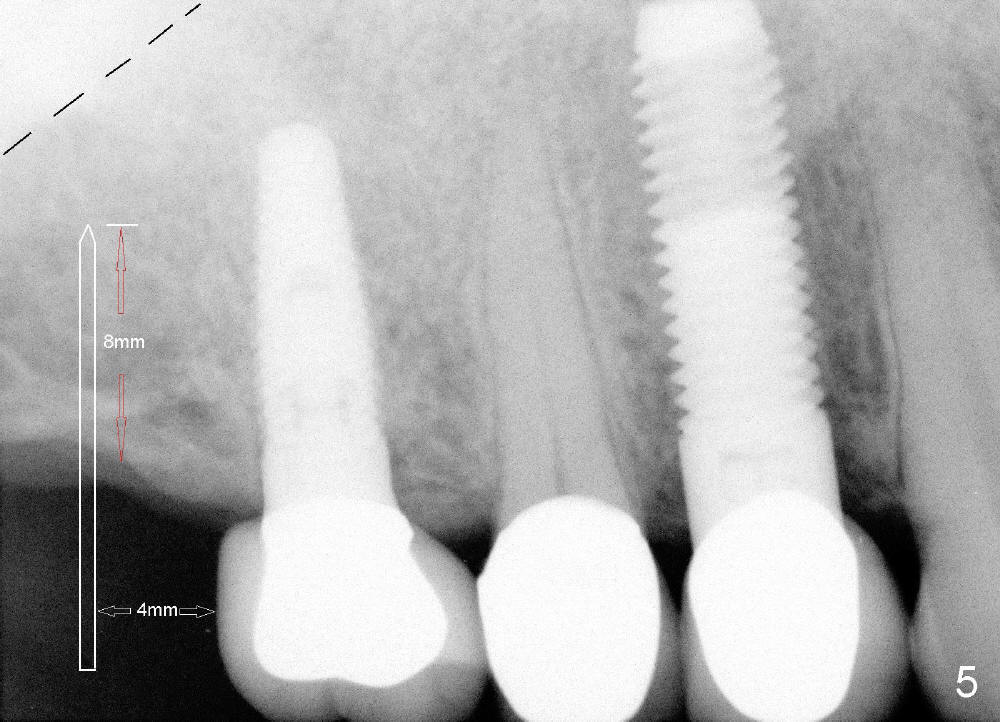

A 71-year-old male is a bruxer. His upper left fixed partial denture was lost 4 years ago (Fig.2). It is replaced by an implant (Fig.3: #14) and two single unit crowns (#13,15). One year later, the tooth #5 is replaced by an immediate implant due to crown fracture (Fig.1,4). Six months after the cementation of #5 implant crown, the tooth #15 is restored by an immediate implant due to root fracture (Fig.6). Recently, porcelain chips off the PFM crown of #13. The patient finally agrees to have another implant (Fig.1: #2) to make his dentition complete and distribute masticatory force more evenly.

The advantage to place implants for a bruxer is that there is sufficient bone height (Fig.2-4). The bone density also appears to be high; there is a thick cortical bone in the edentulous ridge of #2 (Fig.4 arrowheads). Incision will be made; suture may be required for flap fixation. Osteotomy is initiated by 2 mm pilot drill 4 mm from the neighboring tooth (Fig.5); the depth is 8 mm. The depth of the osteotomy is adjusted according to X-ray taken with a parallel pin. Sinus lift may be needed (Fig.5 dashed line: sinus floor). The density of the cancellous bone will be felt and determined while using the 2 mm pilot drill for initial osteotomy. If the density is high, Bicon reamers will be used for further osteotomy and bone saving. Otherwise, osteotomy will be finished mainly with Bone Expander Kit or osteotomes. Bone-level implant is used, followed by a healing abutment. Decortication will be done with a surgical handpiece with a fissure or round bur. If no suture is used for flap fixation, perio glue will be used to close the incision without perio dressing. If the wound is not approximated each other well with sutures, perio glue can be used for complete seal.

Further search of the patient's files finds X-ray taken prior to #5 extraction (Fig.7). Bone height is estimated 12 mm. Since the mesiodistal width of the 1st molar is less than 10 mm (Fig.8), the center of the osteotomy at the site of #2 should be 4.5 mm (3.5 mm from the 2 mm pilot drill). If the bone allows, 5.3x12 implant will be placed.